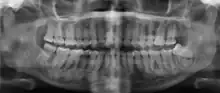

Florid osseous dysplasia of the mandible

xray and CBCT scans of periapical cemental dysplasia